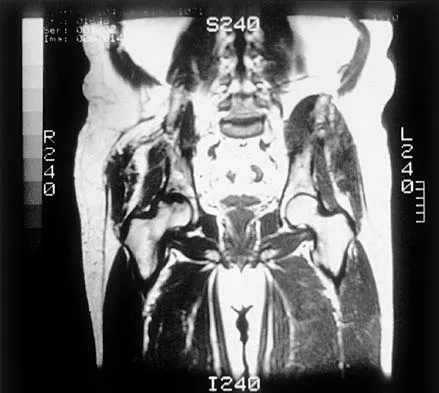

An otherwise healthy 70-year-old man has back and bilateral leg pain in an L5 distribution that is aggravated by standing more than 10 minutes or walking more than 100 feet. He has to sit to get relief. Neurologic and pulse examinations are normal. A radiograph and MRI scan are shown in Figures 4a and 4b. Treatment should consist of

Explanation

The patient has a degenerative spondylolisthesis at L4-5 with associated spinal stenosis. His symptoms are consistent with neurogenic claudication. Based on these findings, the surgical treatment of choice is decompression and posterolateral fusion. Use of instrumentation is controversial. Laminectomy alone is reserved for the patient who is frail medically. There is no role for an anterior approach or for fusion alone without decompression. Fischgrund JS, Mackay M, Herkowitz HN, et al: Degenerative lumbar spondylolisthesis with spinal stenosis: A prospective, randomized study comparing decompressive laminectomy and arthrodesis with and without spinal instrumentation. Spine 1997;22:2807-2812.